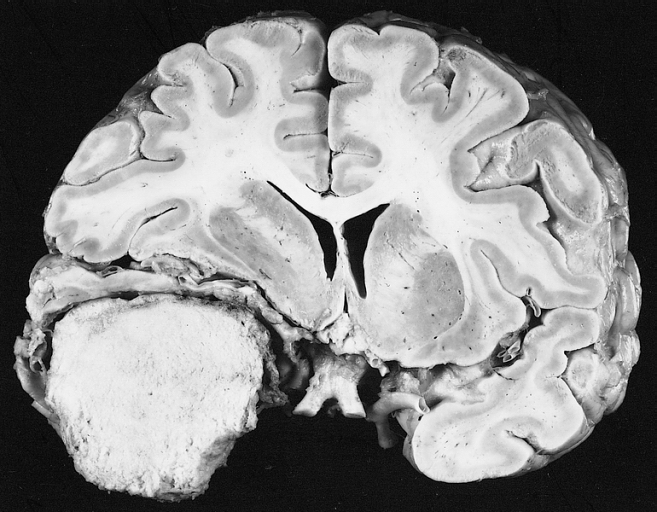

A meningeoma egy olyan daganat, amely az agyat körülvevő és védő háromrétegű szövetben, az úgynevezett meninge-ben (agyhártya) alakulhat ki a meningeális sejtek felszaporodásának következtében. Lassan növekvő, többnyire jóindulatú elváltozás, amely sok esetben csak megfigyelést igényel, azonban a bonyolult szövettani felépítésű vagy veszélyeztető helyen elhelyezkedő meningeomák esetében műtétre vagy a gamma-késes kezelésre lehet szükség.

A meningeoma az intracranialis (agyban lévő) daganatok leggyakoribb típusa, a központi idegrendszeri daganatok több, mint egyharmad részét teszi ki. Kialakulásának kockázata az életkor előrehaladtával emelkedik, a betegek átlagos életkora a diagnózis idején megközelítőleg 66 év. Gyermek- és fiatal felnőttkorban a meningeoma előfordulása ritka, az elváltozás nőknél gyakrabban fordul elő, mint férfiaknál.